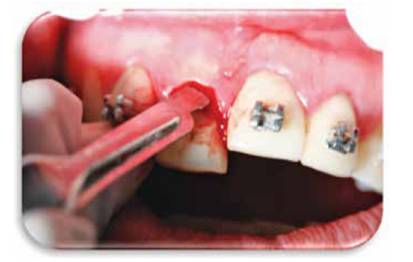

Se realiza control 1 mes despúes y se determina que es necesario rea- lizar una fibrotomía para ayudar en el proceso de extrusión rápida. (Figura 11)

Se hace una fibrotomía para ayudar al proceso y se deja ferulizado por 4 meses. (Figura 12)

Figura 12: Se muestra la hoja de bisturí aplicada al periodonto para poder realizar la fibrotomía.